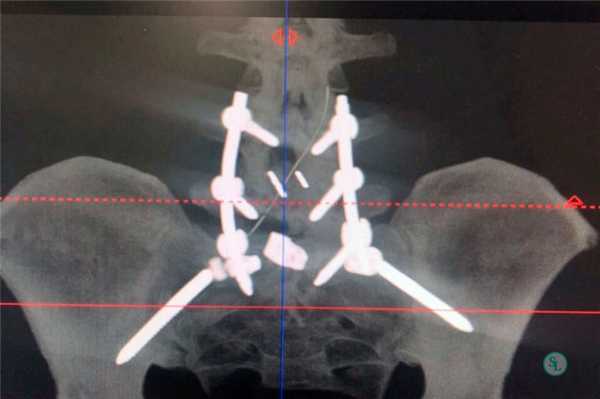

Стабилизационная система на рентгене.

В большинстве случаев проблемный сегмент стабилизируют с помощью металлоконструкций, чаще представленных транспедикулярными системами и пластинами с винтами из высокотехнологичных сплавов металла. В хирургии такая техника называется инструментацией позвоночника. Кроме металлоконструкций, для стабилизации также могут быть применены полимерные устройства, сделанные, например, из углеводородного волокна или резорбирующегося высокомолекулярного биополимера. К отдельной разновидности стабилизирующих вмешательств, которые не причисляют к инструментации, относят установку кейджей имплантатов межпозвоночных дисков.

Стабилизация поясничного отдела.